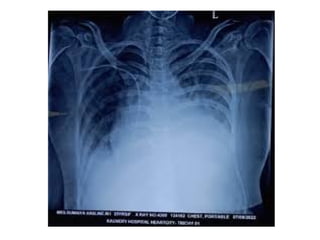

 Chest x-ray: shows the signs of cardiomegaly

 Chest x-ray: shows cardiomegaly

 History  Echocardiography Chest x-ray: shows the signs of cardiomegaly  ECG: reveals tachycardia, bradycardia and dysarrythmias.  Cardiac catheterization: it is performed to confirm CAD DIAGNOSTIC MEASURES

 Chest x-ray:shows cardiomegaly  ECG: shows tachycardia  Echocardiography : for the visualization of left ventricle  CT-Scan and MRI Scan INVESTIGATIONS